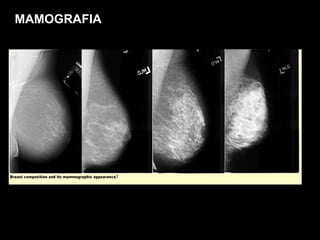

MAMOGRAFIA

RESSONÂNCIA MAGNÉTICA DA MAMA